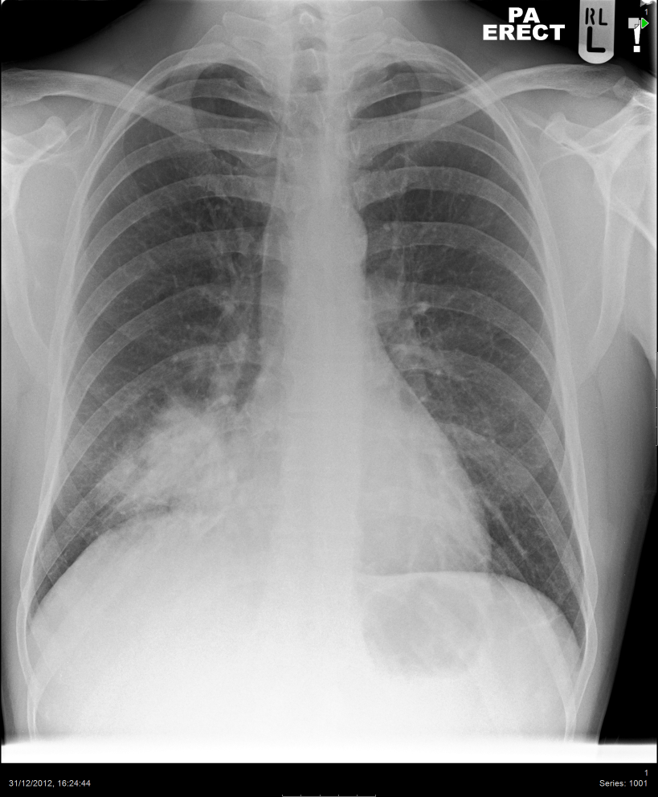

Cough for 3 weeks

Normal (3)